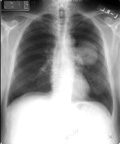

Νέα Υόρκη: Οι γυναίκες που καπνίζουν είναι πιθανότερο να εκδηλώσουν καρκίνο των πνευμόνων συγκριτικά με τους άνδρες καπνιστές, ωστόσο είναι επίσης πιθανότερο να επιβιώσουν της νόσου, σύμφωνα με νέα στοιχεία που δημοσιεύονται στο επιστημονικό έντυπο Journal of the American Medical Association.